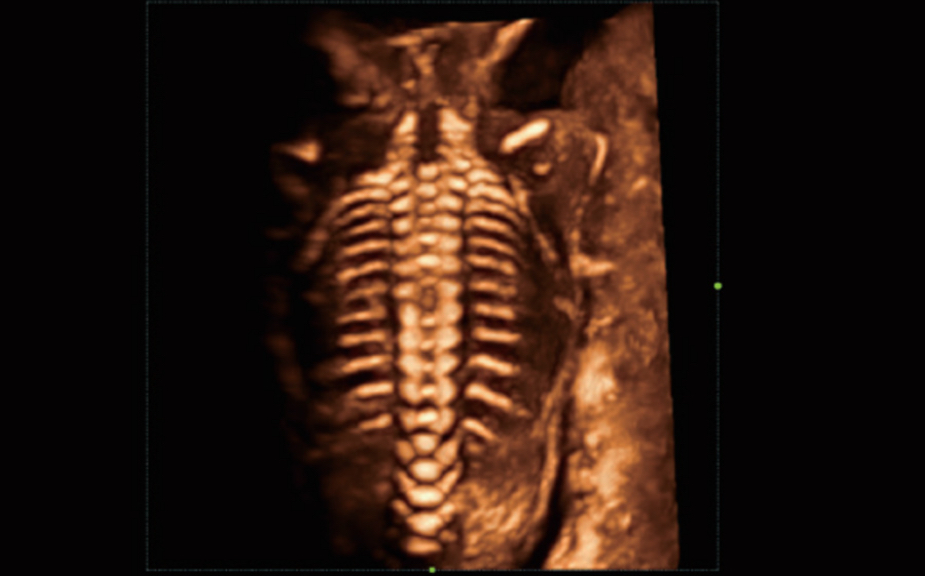

Le Nuewa?I9, con?u spÃĐcialement pour la santÃĐ de la femme et les soins nÃĐonataux, offre une expÃĐrience entiÃĻrement nouvelle gr?ce aux innovations dont il est dotÃĐ, tant à lâintÃĐrieur quâà lâextÃĐrieur. Ces innovations sont dÃĐveloppÃĐes sur la base d'une comprÃĐhension approfondie de scÃĐnarios cliniques complexes, fournissant des rÃĐponses prÃĐcises et adaptÃĐes ainsi qu'une efficacitÃĐ exceptionnelle et une expÃĐrience utilisateur remarquable.

La plate-forme ZST+?est une innovation extraordinaire, reprÃĐsentant une ÃĐvolution de lâimagerie ultrasonore. Elle transforme la formation conventionnelle de faisceaux en un traitement basÃĐ sur les canaux de donnÃĐes. Elle repousse les limites de lâimagerie conventionnelle et du compromis entre rÃĐsolution spatiale, rÃĐsolution temporelle et uniformitÃĐ tissulaire en offrant une qualitÃĐ dâimage exceptionnelle pour des solutions dâimagerie infinies et en constante ÃĐvolution.